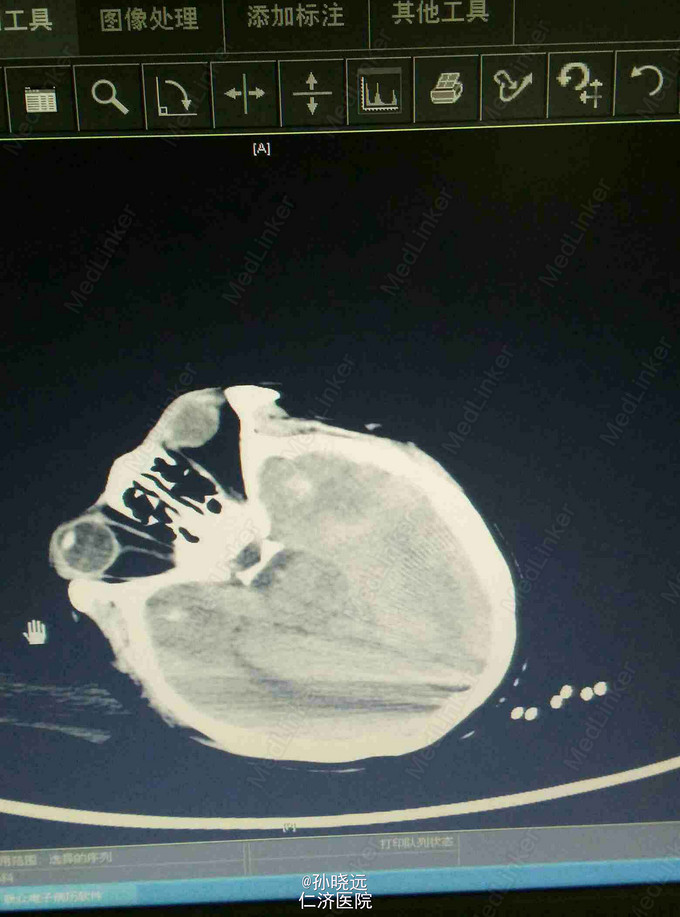

中年女性。主诉:头晕三天,发热伴神志不清1天。 患者于三天前出现持续性头晕,无恶心、呕吐,无视物旋转,来院就诊,查头颅MRI未见异常,予桂哌齐特、长春西汀、硫辛酸治疗,症状无好转。1天前出现高热,最高39.5℃,无咳嗽、气促,再次来院就诊,查血常规:WBC:5.85*10^9/L,N:71.8%,CRP正常,予退热,阿奇霉素等治疗,今日凌晨出现神志不清,无抽搐、恶心、呕吐,头颅CT示两侧颞底部不规则斑点样密度增高影并周围低密度灶,考虑脑炎合并灶性出血,予更昔洛韦、醒脑静、喜炎平、奥美拉唑、甘露醇治疗。后出现氧饱和度下降,予气管插管有创呼吸机辅助通气。 既往史:曾有高血压病史,未应用降压药。

查体:T:39.7℃,BP:180/120mmHg,神志不清,无法对答。双侧瞳孔等大等圆,直径0.15cm,对光反射迟钝,鼻唇沟对称。颈项强直。四肢肌张力正常。肌力检查不合作。双侧膝反射存在。双侧巴氏征阳性。克氏征、布氏征阳性。颈静脉无怒张,气管居中,两肺呼吸音粗,可及少量湿罗音。心率112bpm,未及杂音。腹部查体均正常。

诊断:脑炎。脑出血。 治疗:甲强龙抗炎,更昔洛韦,青霉素钠抗感染,降压,甘露醇、甘油果糖、白蛋白、拖拉塞米里降颅压,呼吸机辅助通气等对症治疗。

腰穿是: 脑脊液生化:葡萄糖:12.18mmol/L,CL:110.9mmol/L,蛋白:222.4mg/dl, 脑脊液常规:淡黄,微混。红细胞:1000*10^6/L,白细胞:1059*10^6/L,潘氏试验阳性(++++),嗜中性粒细胞12%,淋巴细胞:80%,单核细胞8%,凝块无,细菌未找到。 予加用血必净,加强抗感染等治疗。 患者目前仍昏迷,正进行高压氧仓治疗。这是最近一次复查的头颅CT。